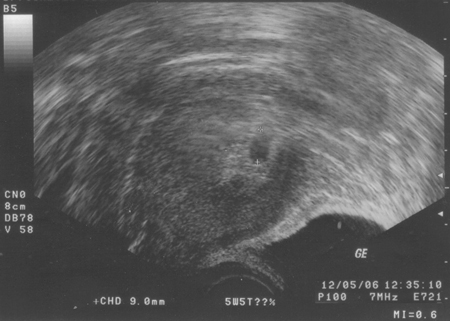

- ca. 17. April 2006

Bienchen und Blümchen ...

- 27. April 2006

Lange Debatte über eine feine Linie... Einer sagt "positiv",

einer sagt "negativ"

- 29. April 2006

Keine Debatten mehr dank eines dicken "+"

- 14. Mai 2006 ... Mamma is schon wieder echt übel ...